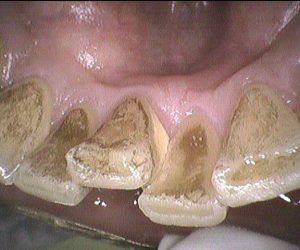

今日のクリーニングです🦷 下の前歯の表側と裏側からみたお写真です📸 歯と歯の間にプラーク(歯垢)や歯石が付着していました。 歯ぐきも少し腫れていて、触ると出血がありました […]

今日のクリーニングです🦷 下の前歯の表側と裏側からみたお写真です📸 歯と歯の間や歯ぐきのきわには歯石がついており、 表面にはステイン(着色汚れ)も付着していました。 クリ […]

今日のクリーニングです🦷 下の前歯の表側、裏側のクリーニング前後のお写真です📸 歯と歯の間や、歯ぐきのきわに歯石が多く付着していました。 歯ぐきも少し腫れていた […]